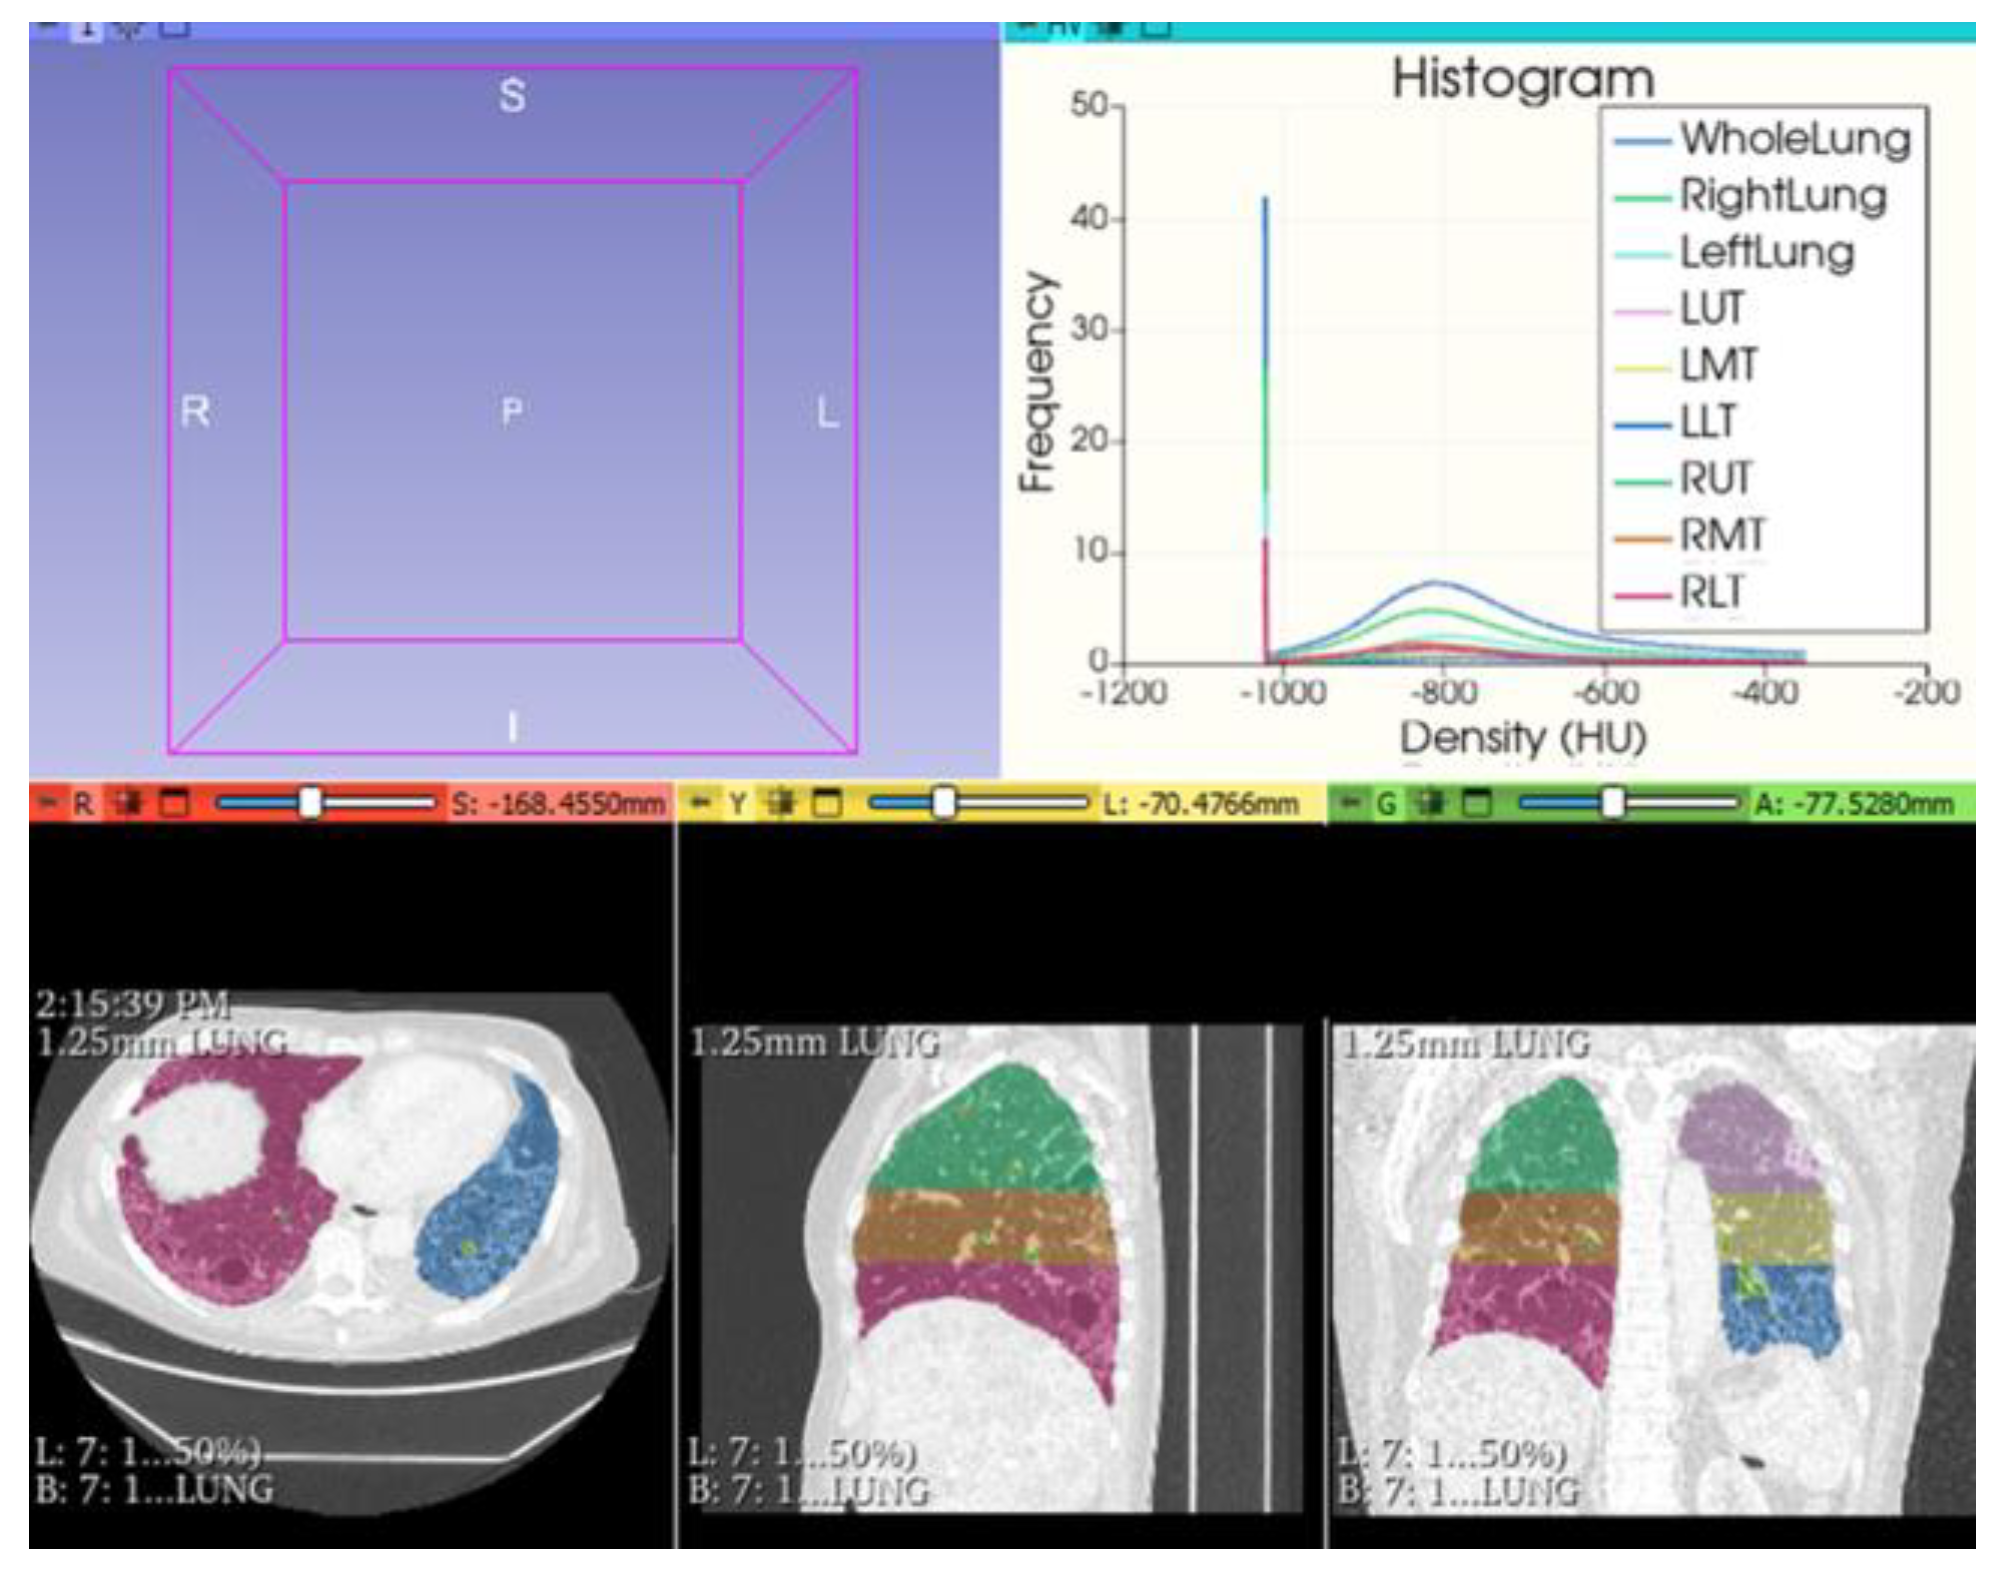

- Rea, G.; De Martino, M.; Capaccio, A.; Dolce, P.; Valente, T.; Castaldo, S. Comparative analysis of density histograms and visual scores in incremental and volumetric high-resolution computed tomography of the chest in idiopathic pulmonary fibrosis patients. Radiol. Med. 2021, 126, 599–607. [Google Scholar] [CrossRef]

- Bocchino, M.; Bruzzese, D.; D′Alto, M.; Argiento, P.; Borgia, A.; Capaccio, A.; Romeo, E.; Russo, B.; Sanduzzi, A.; Valente, T.; et al. Performance of a new quantitative computed tomography index for interstitial lung disease assessment in systemic sclerosis. Sci. Rep. 2019, 9, 9468. [Google Scholar] [CrossRef]

- Camiciottoli, G.; Orlandi, I.; Bartolucci, M.; Meoni, E.; Nacci, F.; Diciotti, S.; Barcaroli, C.; Conforti, M.L.; Pistolesi, M.; Matucci-Cerinic, M.; et al. Lung CT densitometry in systemic sclerosis: Correlation with lung function, exercise testing, and quality of life. Chest 2007, 131, 672–681. [Google Scholar] [CrossRef]